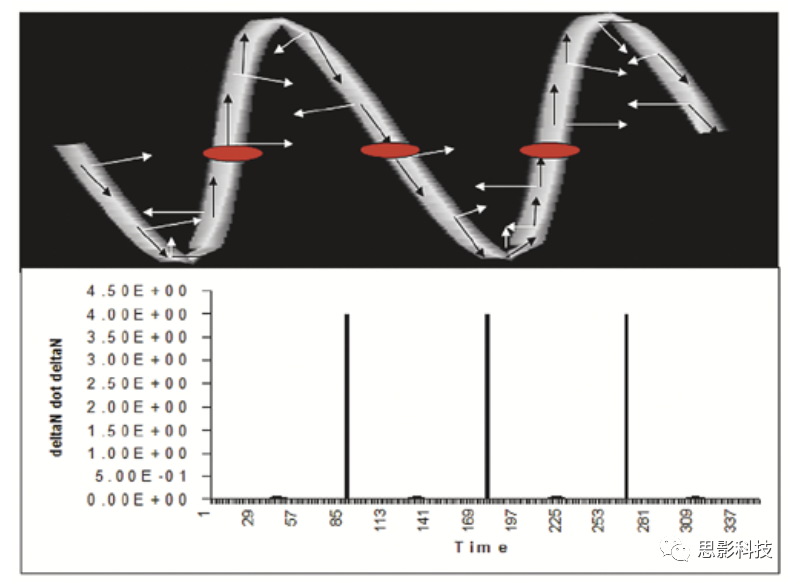

7、IEEE TRANSACTIONS ON MEDICAL IMAGING: MRA图像中颅内血管卷曲度的测量

异常的血管卷曲度、缠绕等特征的识别是临床疾病诊断的重要依据。已有的研究更多地是基于二维图像下,围绕血管的曲折度展开的。而对于三维图像中异常卷曲度的血管建模在医学图像处理中也很重要。

本研究首次提供了三维图像中颅内循环系统卷曲度的识别方式。我们对原有的二维图像下的卷曲度矩阵进行了拓展,并定义了卷曲度异常的三个临床特征。随后对本实验中采集得到的健康对照组和疾病组的三个临床特征进行分析,试图寻找具有异常血管卷曲度的区域。

本研究结果显示,三维的卷曲度能够更为有效地识别出血管形态的异常。基于曲率总和的卷曲度能够有效地识别出血管的缠绕现象,而这种螺旋状的结构与恶性肿瘤有关。

原文:Measuring Tortuosity of the Intracerebral Vasculature From MRA Images

DOI:10.1109/tmi.2003.816964